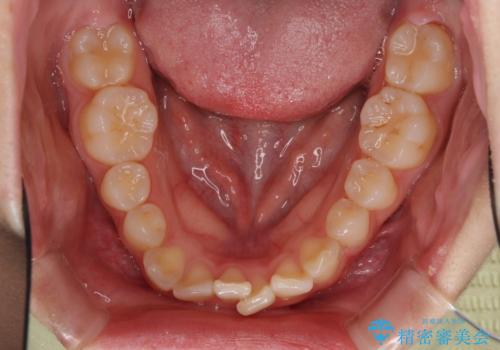

- 八重歯やデコボコをインビザラインで治療したいとのことで来院された患者様です。

インビザライン単体で治療を行うには叢生が強いと判断されたため、事前にワイヤー装置で抜歯矯正を行い、ある程度改善してからインビザラインにて仕上げていくこととしました。